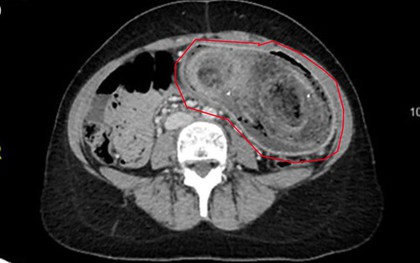

Người đàn ông 33 tuổi bụng phình to như quả bóng, bác sĩ gắp ra thứ "đáng sợ" bên trong

Các bác sĩ đã tiến hành một số xét nghiệm trên nam bệnh nhân 33 tuổi, bao gồm cả nội soi và phát hiện ra thứ "không ai ngờ" trong dạ dày của anh.